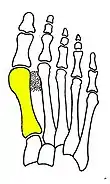

Primus varus deformity

Primus varus deformity is the leaning of the first metatarsal bone away from the second metatarsal and towards the opposite foot (Fig. 1). As it leans over, its head sticks out to form the bunion bump and it also widens the forefoot to cause shoes feeling too tight. Thus when bunion pain becomes unmanageable, surgical correction is to narrow the forefoot by repositioning of the first metatarsal head back to its normal position. This can be done by osteotomy (bone-breaking), soft tissue (non-osteotomy) or fusion techniques.